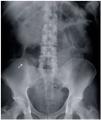

A 66-year-old man with an unremarkable past medical history was admitted to the hospital with symptoms of abdominal pain of 36-hour progression suggestive of acute appendicitis. Laboratory work-up reported: 21,500 leukocytes/cc, neutrophils 84.8%, and the remaining tests were normal. A plain anteroposterior abdominal x-ray showed the presence of 2 radio-opaque, filiform, sharp-ended, metallic objects measuring approximately 5 cm and located in the lower right abdominal quadrant (Fig. 1). During the medical interview, the patient denied having swallowed any type of foreign body in the previous days or months. The diagnosis of intestinal perforation secondary to foreign bodies versus appendicitis secondary to foreign bodies was established. Exploratory laparotomy revealed an approximately 9 cm retrocecal appendix perforated at its middle third section by the protruding tip of a straight pin, with its body and a second pin inside the appendicular lumen. Appendectomy was performed with no complications. The presence of the two foreign bodies inside the appendicular lumen was corroborated in the operating room through x-ray of the specimen (Fig. 2). The histologic report of the specimen was acute appendicitis with abscess and the presence of 2 straight pins in the lumen (Fig. 3). The patient progressed satisfactorily and was released 48 hours after surgery.

Figure 1. AP x-ray of the 66-year-old male patient showing the pins in the appendicular lumen.